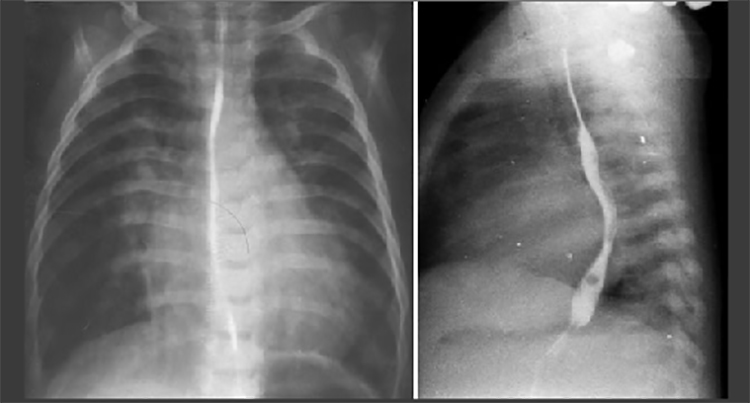

These chest X rays taken during a barium swallow show biventricular enlargement, a large pulmonary trunk, increased pulmonary arterial vascularity and a left aortic arch.

Biventricular enlargement is reflected by the large cardiac shadow extending both leftward and rightward. The PA view demonstrates dilation of the pulmonary trunk manifested by the convex density below the aortic knob. Increased pulmonary arterial vascularity is reflected by dilated central pulmonary arteries and prominent distal arterial vascular markings. A left aortic arch is indicated by deviation of the tracheal air shadow to the right and presence of the aortic knob at the left upper mediastinal border. Note also left atrial enlargement indicated in the lateral view by indentation and posterior deviation of the barium filled esophagus.